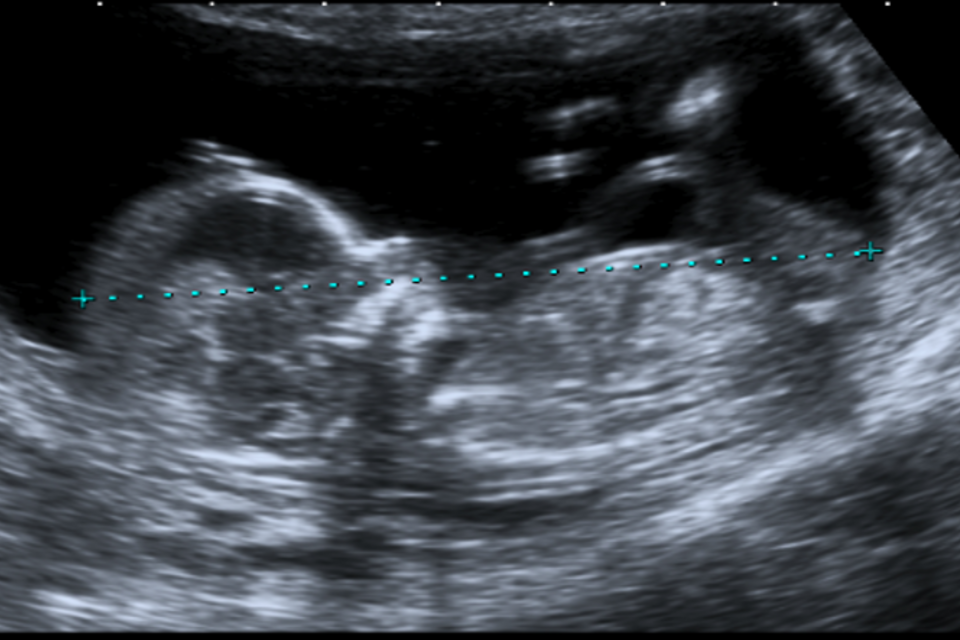

Example 2 shows 2 ultrasound images of a CRL and an NT that do not meet all the criteria. There is also a screenshot of what the accompanying image review tool would look like for both images.

Example 2